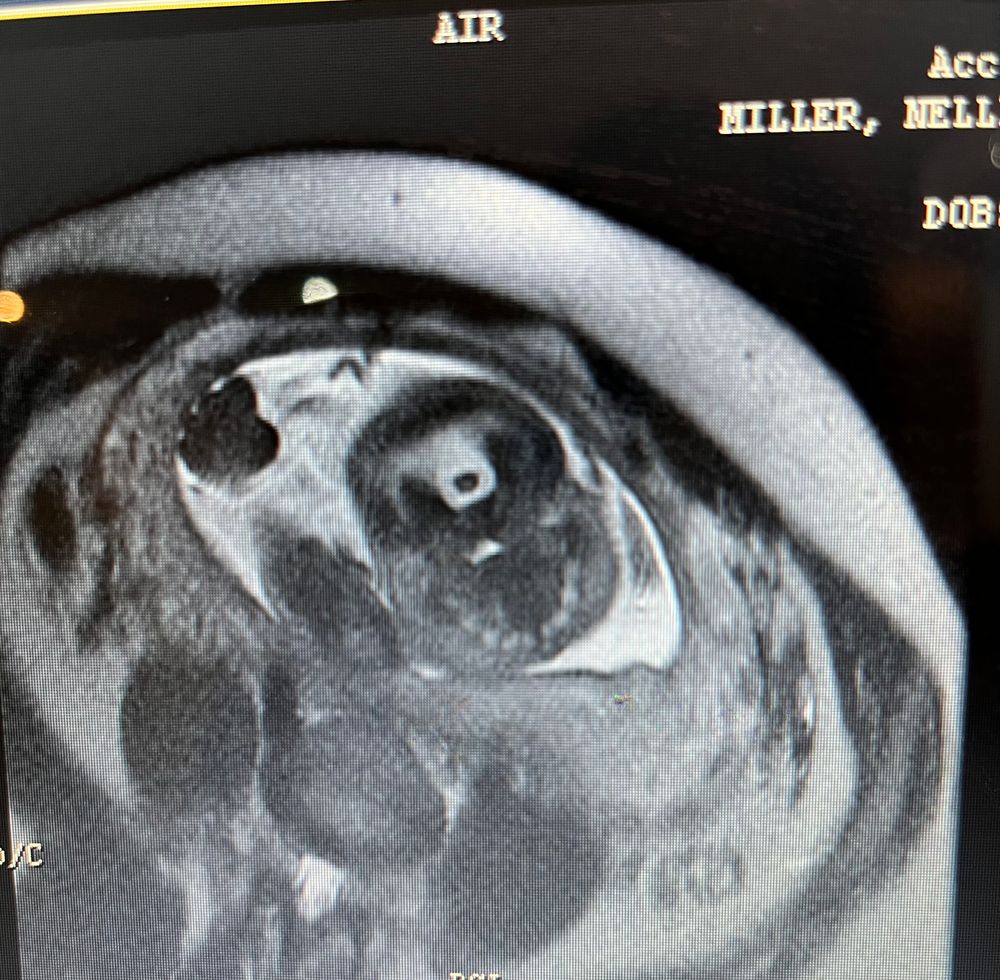

23 УЗИ. МРТ плода. Дексаметазон